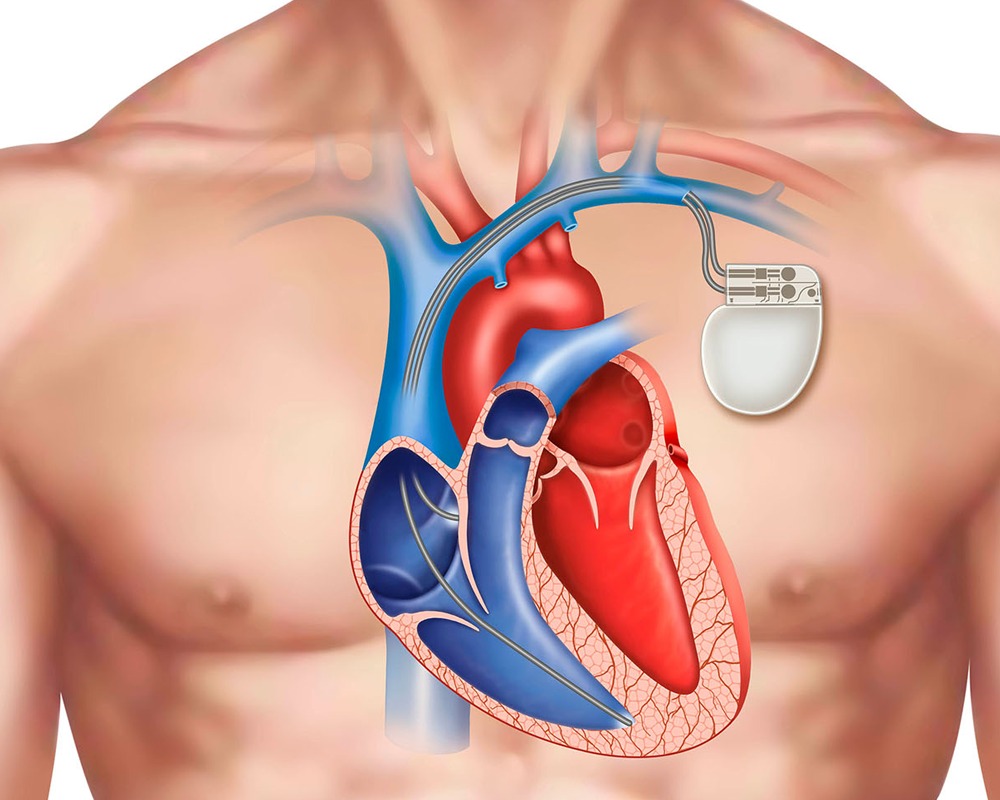

पेसमेकर क्या है और यह दिल की बीमारी में कैसे मदद करता है?

आजकल अनियमित दिल की धड़कनें यानी हार्ट रिदम डिसऑर्डर एक आम समस्या बनती जा रही है, खासकर उम्रदराज लोगों में। इन समस्याओं का इलाज समय पर न किया जाए तो यह गंभीर रूप ले सकती हैं। ऐसी स्थिति में पेसमेकर

पेसमेकर क्या है और यह

आजकल अनियमित दिल की धड़कनें यानी हार्ट रिदम डिसऑर्डर एक आम समस्या बनती जा रही है, खासकर उम्रदराज लोगों में। इन समस्याओं का इलाज समय पर न किया जाए तो...